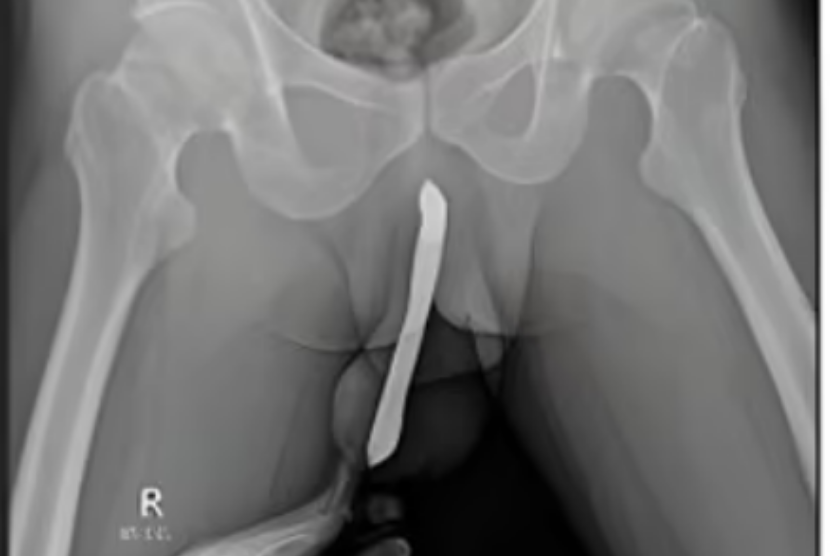

Hasil rontgen memperlihatkan sikat gigi terselip di alat vital seorang pria berusia 43 tahun asal Jawa Timur. Kasus fraktur penis yang dialaminya dilaporkan tim dokter RSUD Dr Soetomo ke International Journal of Surgery Case Reports pada 20 Februari 2024.